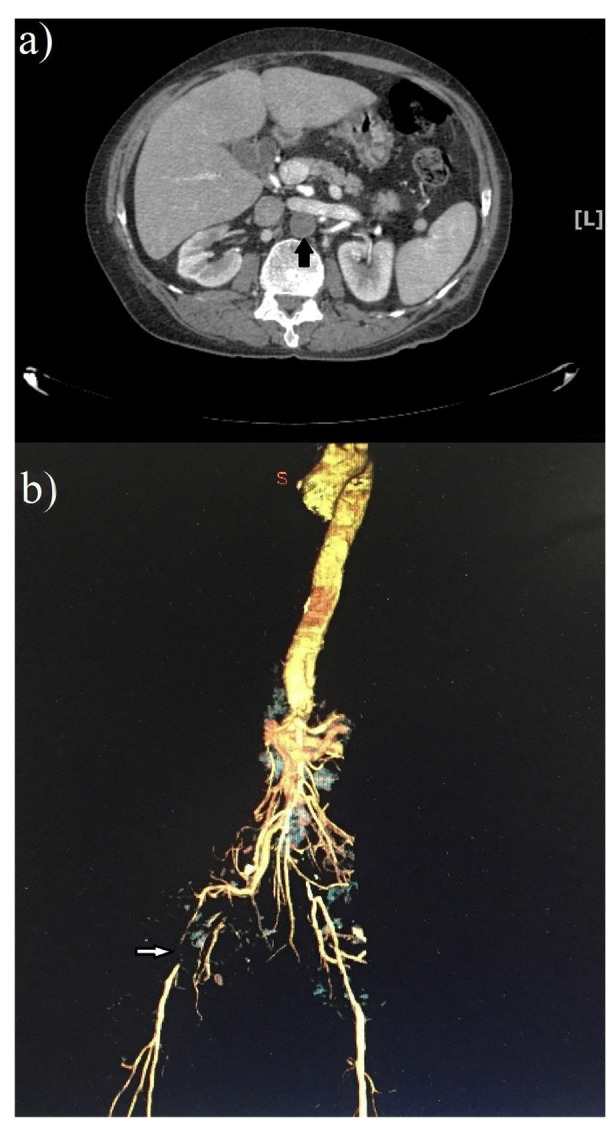

Different side effects have been reported for leech therapy, such as local itching, skin reactions, infection, bleeding disorders, and anemia. The present study described a rare and lethal adverse event following leech therapy. A 63-year-old man was referred to Nemazee Teaching Hospital (Shiraz, Iran) in December 2020 with a two-week history of progressive right lower extremity swelling, erythema, and ecchymosis. One week before symptom onset, he had undergone leech therapy on the lateral calf and upper thigh of the right lower extremity, administered by a traditional healer. Physical examination revealed gangrene of the right leg and absence of all pulses. Color Doppler sonography of the leg and computed tomography angiography (CTA) of the thoracic aorta to the lower extremities revealed complete thrombosis of all right lower extremity arteries, extending to the right iliac artery and abdominal aorta. With a diagnosis of arterial occlusive disease and septic thrombophlebitis, the patient received intravenous antibiotics and anticoagulant therapy. Due to the inadequacy of medical treatments, a right lower extremity amputation was performed. The patient expired 5 days postoperatively due to septic shock and multiorgan failure.